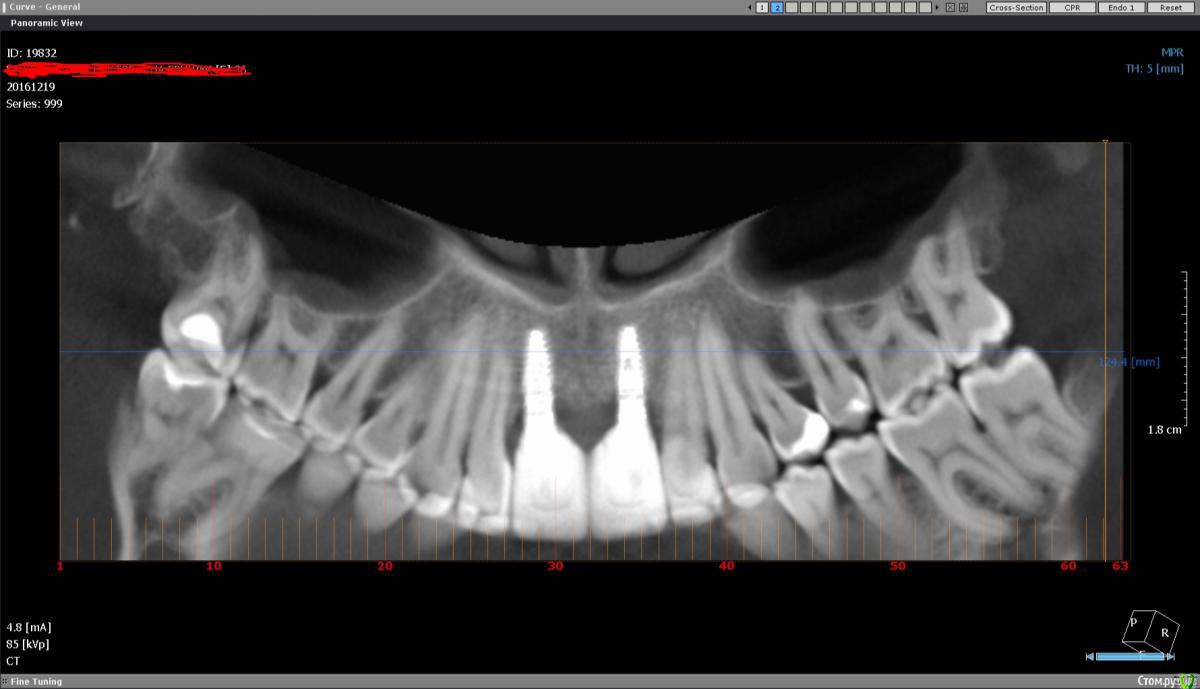

ЕленаR Опубликовано 21 декабря, 2016 Автор Поделиться Опубликовано 21 декабря, 2016 Добрый день. Уже все сделано и нет пути назад. Но хочется услышать ваше мнение и поделиться продолжением своей эпопеи. На приеме врач сразу отправил на КТ.глядя снимки, предположил, что один имплант не стабилен.Поэтому предыдущие врачи сделали сдвоенную коронку. Также сказал, что противник чтобы подсаживали свой костный блок во фронт. Сколько здесь писала про это, никого не удивляло, что мне блок во фронт подсадили. Вообщем вчера мне удалили два импланта, вытаскивали, как мне показалось с трудом. Врач сказал, что импланты стояли в кости на 2/3 и обросли фиброзной тканью. Мне сразу установили два импланта суперлайн и поставили формирователи. Через два дня будут ставить временные коронки, через 3 месяца постоянные. КТ пока выложить не могу, в наличии только тел. Уважаемые специалисты, как вы думаете такой план лечения имеет место быть? И импланты суперлайн хорошо система, это не миниимпланты? До этого стояли xive. Удивило то, что если имплант был меньше чем на половину в кости, почему его так выбивали.Это нормально? Извините за сумбур. Доктор вроде адекватный, но так страшно попасть не в те руки опять. Ссылка на комментарий

ЕленаR Опубликовано 21 декабря, 2016 Автор Поделиться Опубликовано 21 декабря, 2016 Вот это по чеку сделано:операция по установке импланта, установка формирователи,применение остеокондуктора церабон 0.5 г, остеокондуктора колпроект Джейсон 1 мембрана, остеокондуктора коллакон натуральный коллагеном альвеолярный конус 1 шт. Ссылка на комментарий

ЕленаR Опубликовано 1 января, 2017 Автор Поделиться Опубликовано 1 января, 2017 (изменено) Добрый день. А не дали мне снимки. Врача не было, сказали, что это снимки личные, для врача, и они их не выдают. К сожалению врача ждать не было возможности, домой ехать нужно было. На сегодняшний день ситуация такая: десна приподнята, но как бы прилипшая к абатаменту. С передней стороны виден абатамент, с задней все закрыто коронкой. Получается над коронкой спереди, как-бы полумесяцем поднята десна. Воспаления тьфу, тьфу вроде нет. 13 поеду снимать швы, не знаю, что он мне предложит. Приложу свои другие снимки, кт до операции и снимок после операции. Посмотрите пож. что там у меня творится.снимоК.bmp Изменено 1 января, 2017 пользователем ЕленаR Ссылка на комментарий